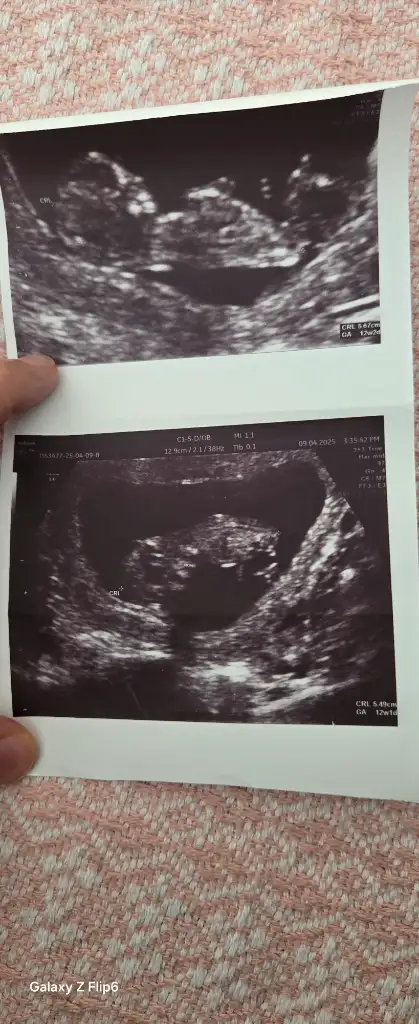

Lütfen bana da bir yorum yapar mısınız. Karından. 13+4 haftalık. İki kızım var erkek olsun istiyorum 🙈

6 haftalik karından ultrasyon tahminde bulunabilir misiniz